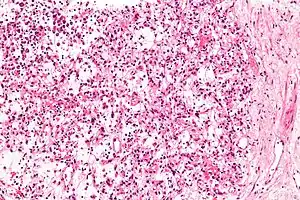

| Micrograph of an inflammatory myofibroblastic tumour of the kidney. Kidney biopsy. H&E stain. | |

Inflammatory myofibroblastic tumours are characterized by a mix of inflammatory cells, e.g. plasma cells, lymphocytes and eosinophils, and bland spindle cells without nuclear atypia. These tumours may have necrosis, hemorrhage, focal calcification and mitotic activity.